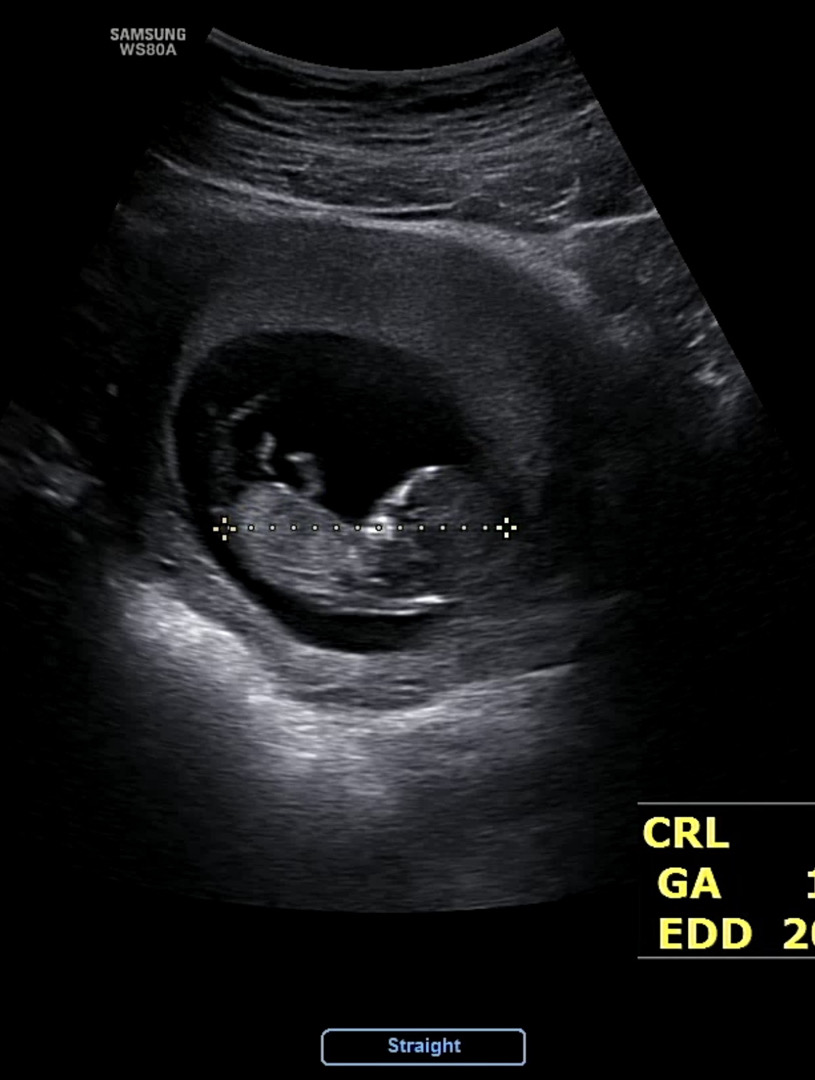

11주2일 각도법 봐주세요

아직은 안보이겠죠?ㅠ

11주는 각도법 보기에 애매할거에용 ㅠㅠ

12주 이상은 되어야겠죠?ㅎㅎ..🤣

넹 ㅎㅎ 저는 12주 1일날 봣는데도 잘 안보여요 ,,, ㅋㅋㅋ

오마나.. 저 다음주에 또 가야해서 기대했는데 아쉽네요😆🥲